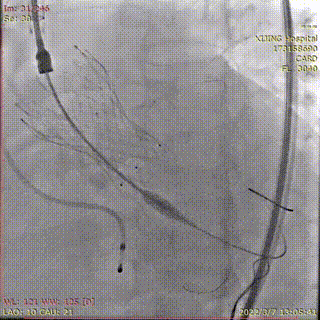

预置4.0*35mm冠脉支架左冠保护并根部造影

22mm球囊预扩张,无漏

送入26mmVenus-A Plus造影定位

释放1/3瓣膜造影检查位置

释放2/3瓣膜

造影检查位置

冠脉支架置于左主干并造影

完全释放Venus-A Plus

烟囱支架扩张释放

造影显示左冠通畅

术后造影显示瓣膜位置理想,冠脉充盈正常